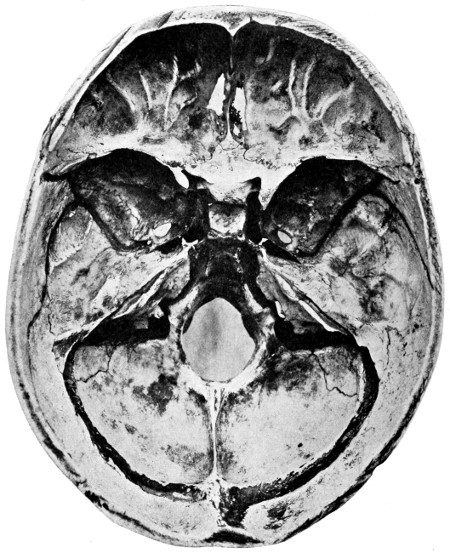

29 A and B. The base of the skull and the base as seen on transillumination 70, 71

30. Plan of the base of the skull 77

50 A and B. The inner aspect of the skull and the same seen on transillumination 137